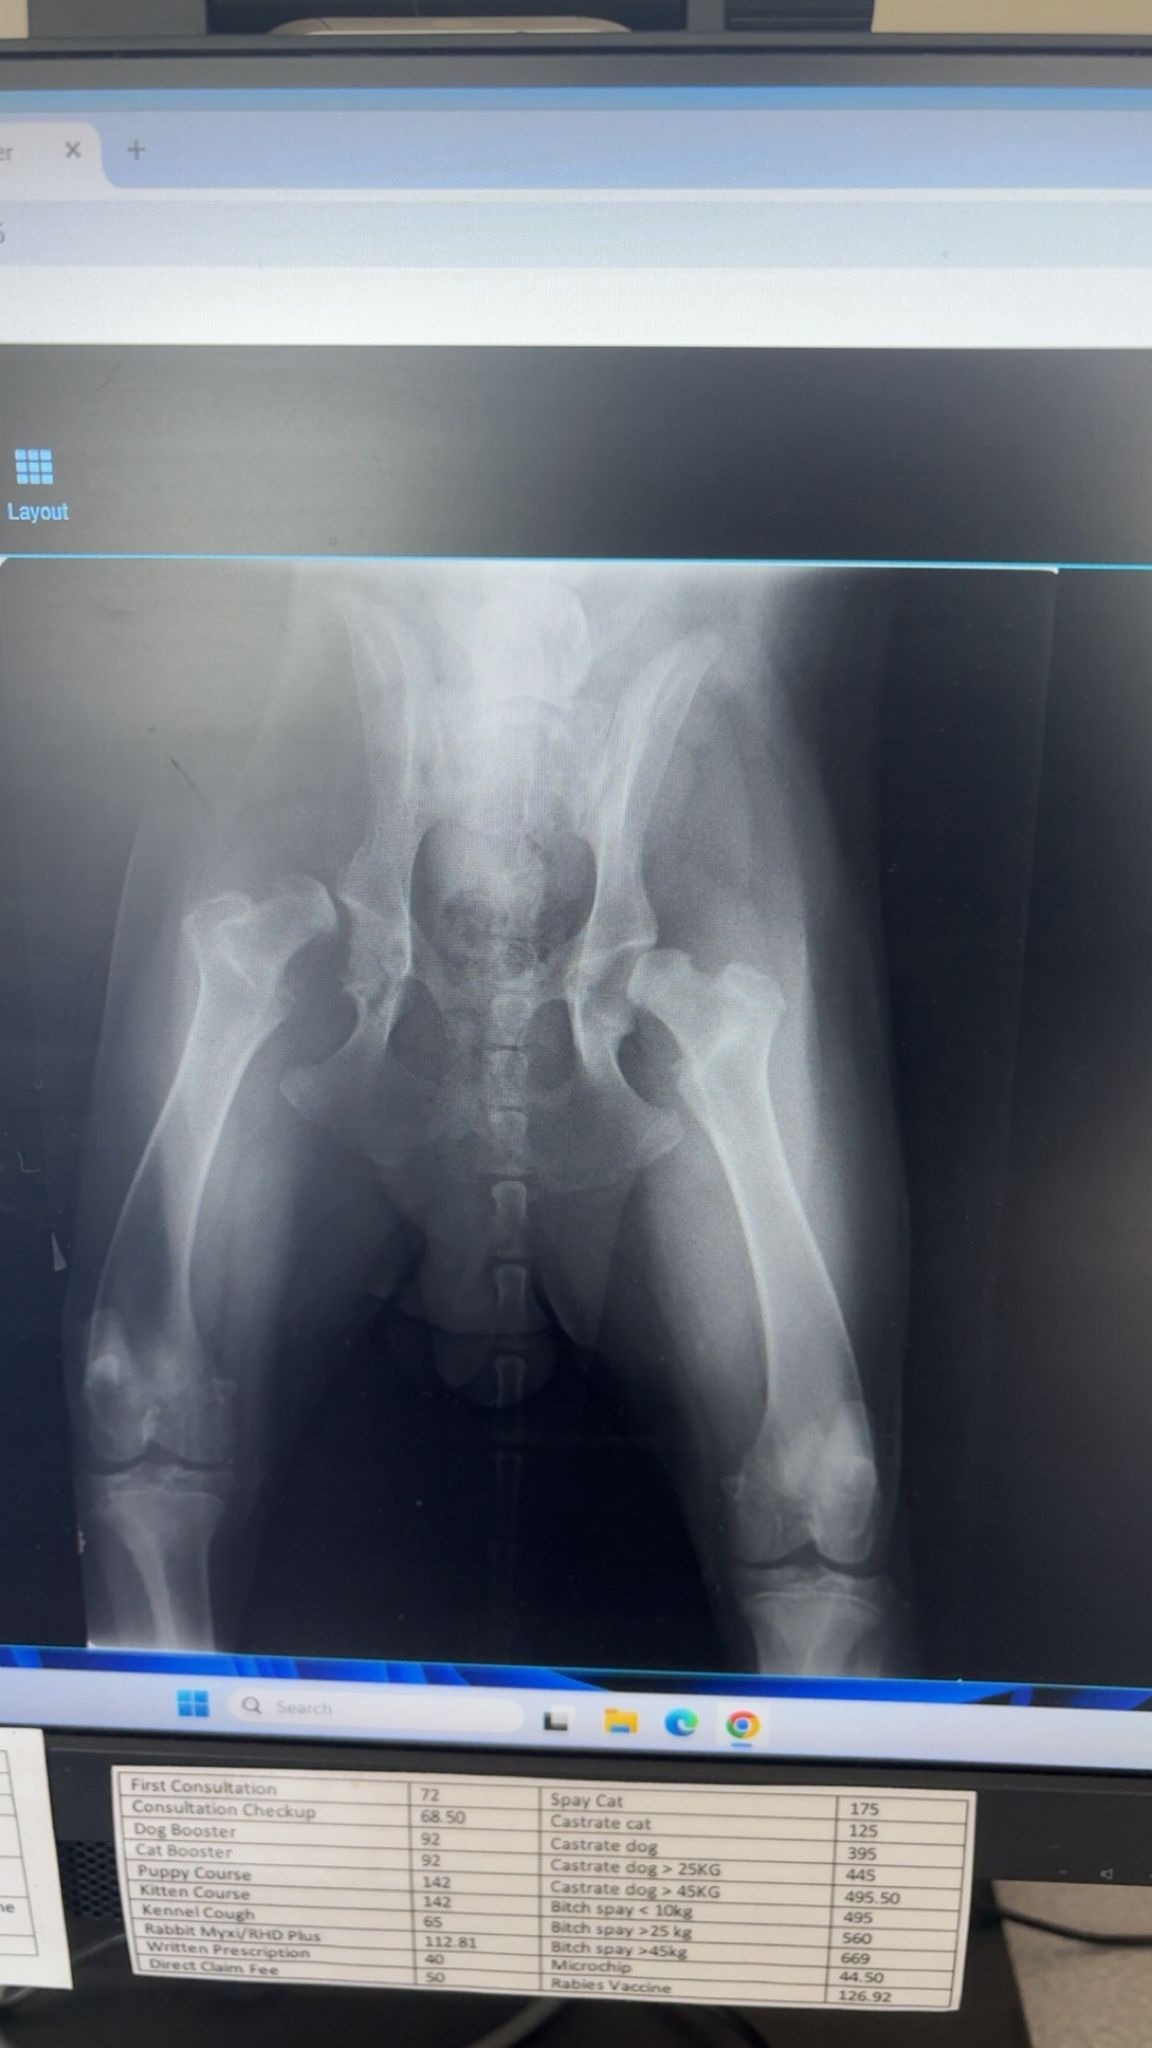

My name is Natasha and my son Tom has a 7 month old German Shepherd called Cairo. Cairo has been diagnosed with severe hip dysplasia, and one of his hips is out of joint with corrosion. This is super rare for his age, but common in his breed.

He is still a baby, and is the most loving, fluffy giant. Without this surgery he will need to be put to sleep. This surgery is something we can't afford at such short notice, but at 7 months old he deserves so much more. Please help us save Cairo and give him the chance to grow up and see more of his life.